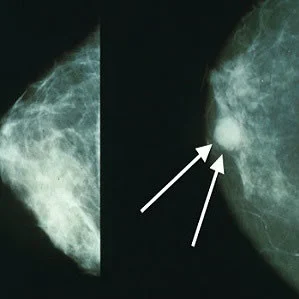

A study conducted by investigators at Brigham and Women's Hospital, the University of York in the UK and MD Andersen Cancer Center in Texas tests the ability of experienced radiologists' to sense when a mammogram is abnormal. The paper is published in  the Proceedings of the National Academy of Sciences.

For the purpose of the investigation, visual attention researchers showed mammograms to radiologists for half a second and found that they could identify abnormal mammograms at better than chance levels. The ability was further tested through a series of experiments in order to determine what signal alerts radiologists to the presence of an abnormality.

While in the clinic, an image is never really assessed in half a second but the point is that these experts have the ability to extract the gist of an image very quickly. In a previous study, Wolfe and his colleagues found that radiologists could detect abnormal mammograms after a half-second glimpse but non-experts could not do the same. In this new study, the researchers tested whether breast tissue symmetry, breast density, image size, resolution or other characteristics were contributing factors to the success rate of the radiologists.

Findings show that performance is not dependent on breast symmetry or breast density but on other finer details related to the texture of the breast tissue. However, the study shows that radiologists can do better than chance in discriminating breast cancer cases from normal tissue, even when the images of abnormal breast tissue did not directly capture a cancerous lesion or when those images were taken from the contralateral breast.

"These results suggest that there may be something in the nominally normal breast that looks abnormal and is detectable," said Wolfe. "Together, these results suggest that radiologists may be picking up on some sort of early, global signal of abnormality that is unknown to us at this point."